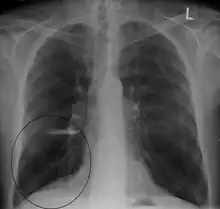

A chest X-ray and complete blood count may be useful to exclude other conditions at the time of diagnosis.[82] Characteristic signs on X-ray are hyperinflated lungs, a flattened diaphragm, increased retrosternal airspace, and bullae, while it can help exclude other lung diseases, such as pneumonia, pulmonary edema, or a pneumothorax.[83] A high-resolution CT scan of the chest may show the distribution of emphysema throughout the lungs and can also be useful to exclude other lung diseases.[25] Unless surgery is planned, however, this rarely affects management.[25] A saber-sheath trachea deformity may also be present.[84] An analysis of arterial blood is used to determine the need for oxygen; this is recommended in those with an FEV1 less than 35% predicted, those with a peripheral oxygen saturation less than 92%, and those with symptoms of congestive heart failure.[24] In areas of the world where alpha-1 antitrypsin deficiency is common, people with COPD (particularly those below the age of 45 and with emphysema affecting the lower parts of the lungs) should be considered for testing.[24]